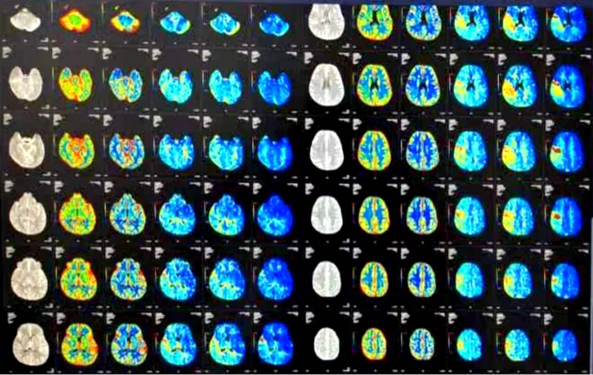

治疗前筛查CTP

OPTION研究是应用注射用重组TNK组织型纤溶酶原激活剂静脉溶栓治疗延长时间窗急性非大血管闭塞性卒中研究,它具有多中心、前瞻性、随机、开放标签、终点盲法研究,OPTION项目的技术方法、国内外的研究背景及创新性。目前对于发病4.5小时脑卒中的患者治疗,国内外都有成熟的指南共识;而对于4.5-24小时非大血管闭塞的脑卒中患者,目前国内外治疗的方法有限。随着影像技术的发展,目前可以识别卒中发作24小时内可挽救的缺血脑组织,而通过静脉溶栓实现再灌注有可能改善4.5-24小时内的临床预后。